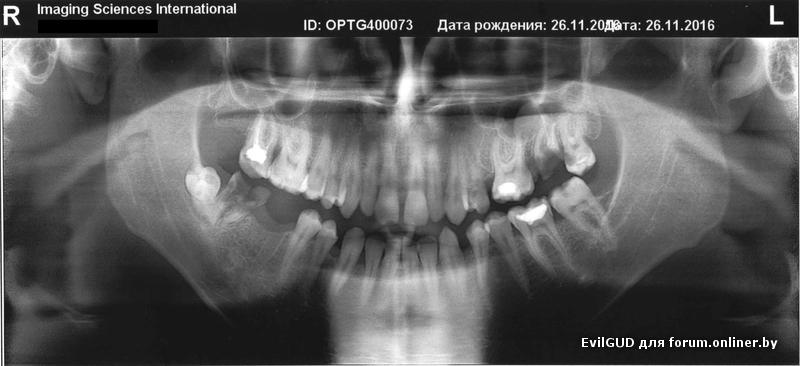

Доброго дня.

Вниз предложили 2 импланта. Верх - мост на 5 шт (отсутствующий 5, удаляемый 7 + соответственно 8,6 и 4)

Одобрите/опровергните?

+ буду благодарен за хорошие ссылки с инфой по видам, плюсам/минусам того или другого вида имплантации, производителей имплантов. А то тексты на сайте каждой стоматологии, но где норм. а где просто сайт наполняли несведущему непонять... вплоть до того, что прямо противоречащую информацию можно встретить.

Спасибо.

EvilGUD:

низ 2 импланта, верх - удалять 27, а далее синуслифтинг с имплантом. 25 не трогал бы. В пазухе над 27 есть подарок от этого зуба в виде кисты.

По имплантам - любые двухэтапные.